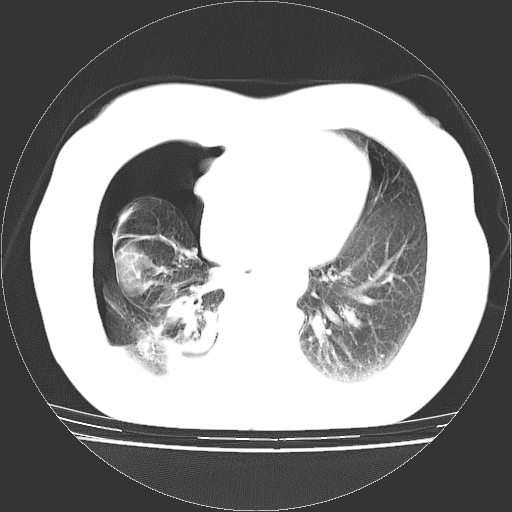

以下是引用zhangzhongshou在2008-3-22 12:52:00的发言:[br]1、右侧液气胸。[br]2、腹水。建议进一步检查。

以下是引用鲁巨ct在2008-3-22 14:10:00的发言:[br]1、右侧液气胸,右中下叶节段性不张。[br]2、腹水,建议上腹部ct检查

以下是引用zjzjr在2008-3-22 17:19:00的发言:[br]1、右侧液气胸,右下叶节段性不张。[br]2、腹水,建议上腹部ct检查